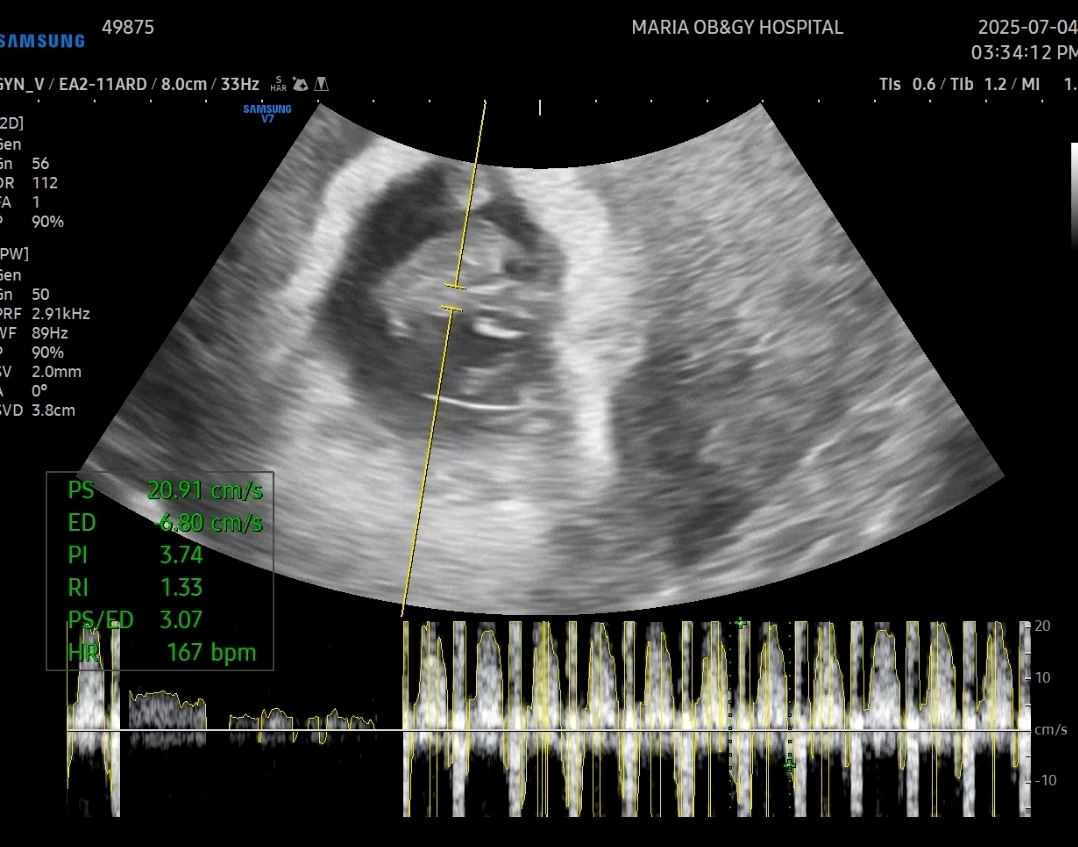

입덧약 받는 김에 본 초음파에서 아기크기는 1.64cm로 실제 8주0일 크기였다 ㅋㅋ 쑥쑥 잘 크고 있군!!

심장소리도 167bpm으로 주수에 맞게 아주 잘 뛰고 있었다!!